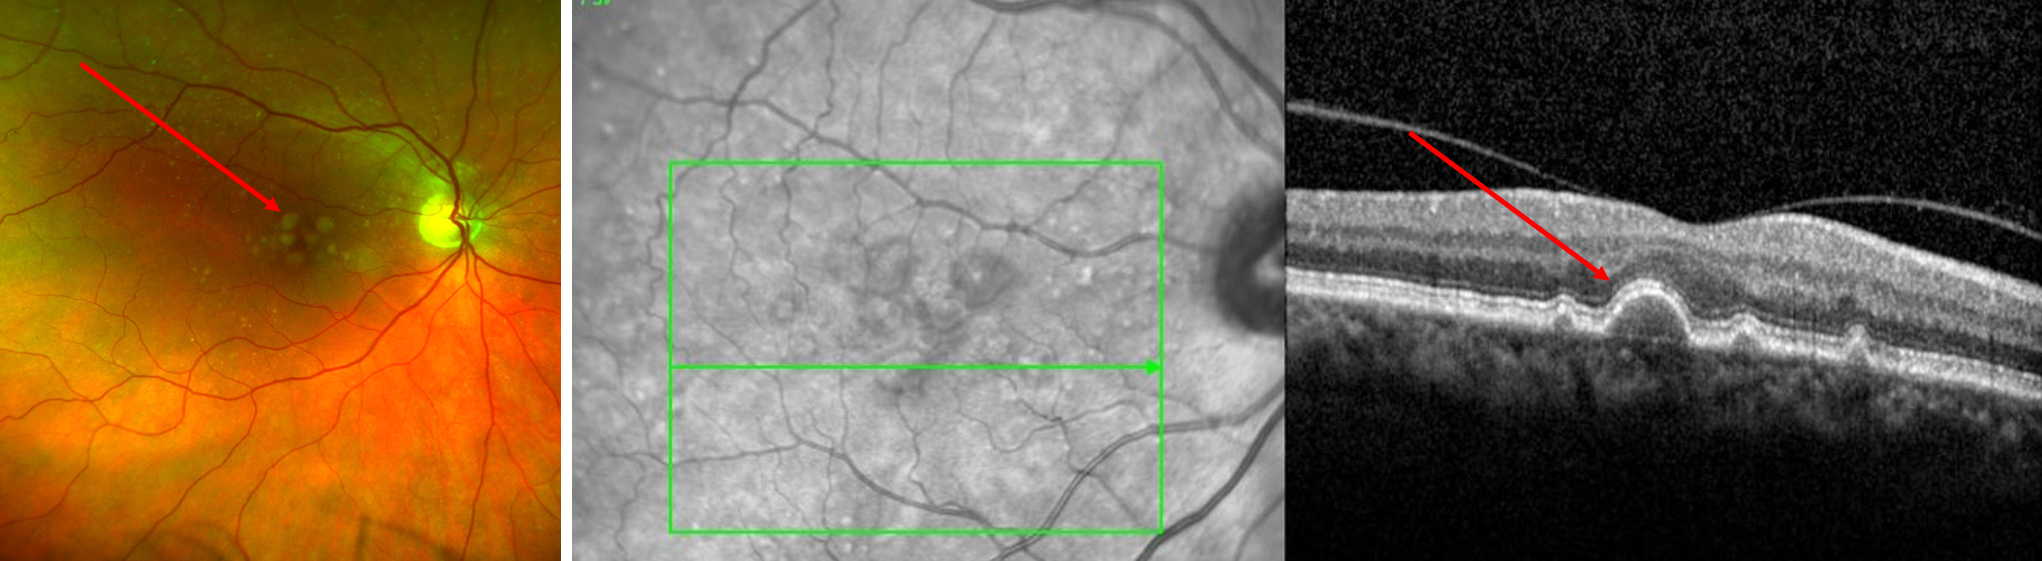

- Dry age-related macular degeneration (dry AMD)

- Milder, earlier, more common form of AMD

- Age-related deposits accumulate in the retina, causing mild to moderate vision symptoms

- In late stages, tissue loss (called “atrophy” or “geographic atrophy”) can occur, resulting in severe vision loss

- The dry form can convert to the wet form at any time

- Dilated retinal examination

- Optical coherence tomography (OCT) scan: painless photograph that provides a cross-sectional scan through the macula so that microscopic details of the macula can be discerned